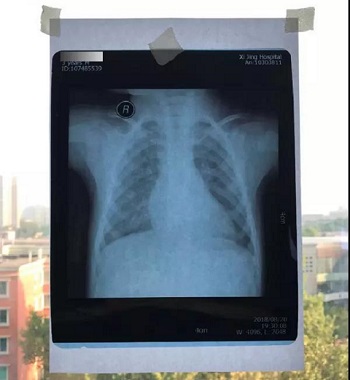

七、将白纸或白布贴于窗户玻璃上,然后将X光片或磁共振或CT片子贴于白纸或白布上。如果用的是电脑显示器翻拍片子,则按照上一条方法将显示屏变白色后,将片子贴于显示器上进行拍照。拍照时一定要正对着片子拍,注意横平竖直,拍端正了,不要拍歪斜了。

十二、拍摄时,尽可能的将片子上的文字信息拍摄清楚,并将左右拍摄清楚(片子上有标R,表示右侧right,L, 表示左侧left的意思), 每张片子上的文字都能按照阅读习惯拍正确,不要拍反了。

拍摄时,必须要对着片子上的文字对焦, 方向正确,将文字拍摄得清晰可视,保证放大图片后文字依然清晰可见(如下图),尽可能多的保留片子上的信息。